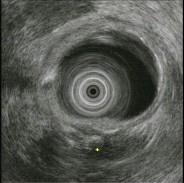

问题 女,55岁,腹痛便秘8年,大便干结伴排便不尽感,35天一次大便,无脓血便及恶心呕吐,食纳如常,体检无异常,结肠镜检查如图。患者哪种疾病可能性最大 ( )

选项 A、肠结核 B、溃疡性结肠炎 C、肠易激综合征 D、肠梗阻 E、结肠癌

答案 C